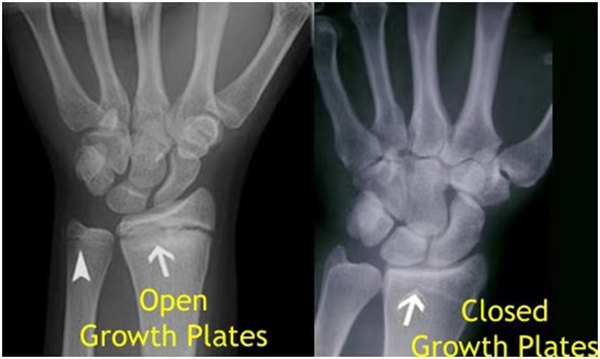

其實想要了解孩子的生長發(fā)育情況或者說孩子未來身高的趨勢,測骨齡是個好辦法。臨床上通常拍攝兒童的左手正位X光片 , 采用《中華-05》骨齡標(biāo)準(zhǔn)對手腕骨發(fā)育程度進行骨齡評價。